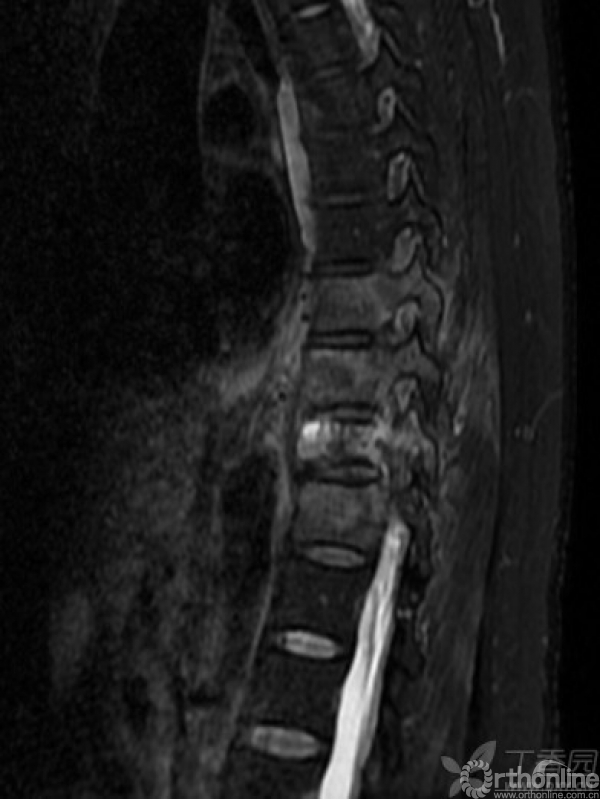

胸椎多椎体病变,如果诊断和治疗?